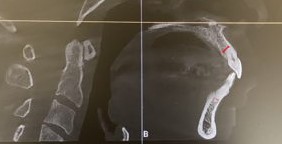

(上顎前歯部では、赤い矢印が範囲内)

この画像示す白い部分が皮質骨

中の多孔質な部分が海綿骨

CTや側方セファロなど精密検査時に撮影したデータでは

単に歯列を見るのではなく

- 歯根と歯槽骨(特に皮質骨)との距離

- 歯がどの方向に動いたときに骨から逸脱するか

- 前歯部にどれだけ前後的、唇舌的余裕があるか

- 臼歯部の骨幅と歯根の位置関係

といった点を、断面ごとに確認・分析をします。

CT撮影では歯を動かした際に歯根と歯槽骨の関係がどう変化するのかを

事前に評価することができます。

例えば前歯部では

見た目ではまだまだ余裕がありそうに見えても

CT上はすでに歯根が皮質骨に近接していることがあります。

この状態で、非抜歯で並べる、拡大する、さらに前に出す

といった治療を行うと、

歯は歯槽骨の外へ押し出されてしまい

先にも述べた不可逆的なトラブルに繋がります。